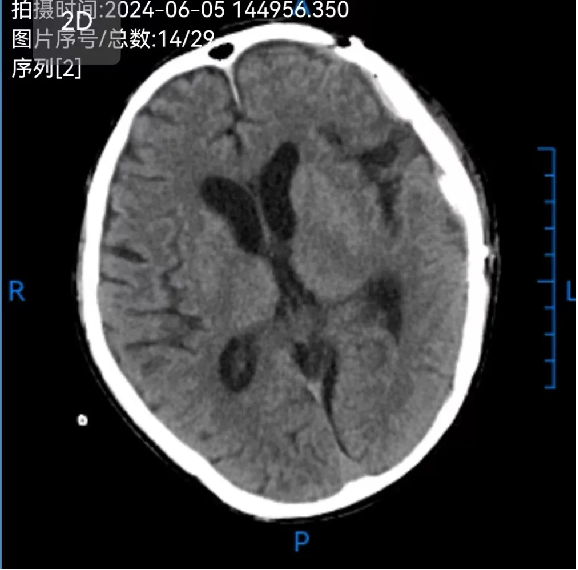

术前: